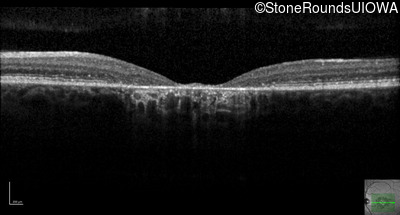

AR Stargardt Disease (IIA)

Age at visit:

45 years

OD

OS

20/200 -2 sc

OCT Stack

AR Stargardt Disease

ABCA4

Val1854Leu GTG>TTG

Gly1961Glu GGA>GAA

AR